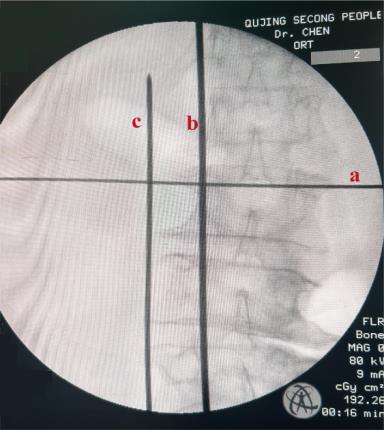

• 单通道非同轴脊柱内镜经椎间孔外入路(椎板外切迹)治疗极外侧椎间盘突出症的临床疗效观察

摘要:目的 观察单通道非同轴脊柱内镜经椎间孔外入路(椎板外切迹)治疗极外侧椎间盘突出症(FLLDH)的临床疗效。方法 回顾性分析2022年5月-2024年5月该院收治的,行单通道非同轴脊柱内镜经椎间孔外入路(椎板外切迹)治疗的FLLDH患者70例。于术前和术后,评估腰腿疼痛程度、腰椎功能和临床疗效。结果 相较于术前,术后3 d和3个月,患者下肢视觉模拟评分法(VAS)评分、腰部VAS评分、Oswestry功能障碍指数(ODI)、数字分级评分法(NRS)评分和Roland-Morris功能障碍问卷(RMDQ)评分明显降低,日本骨科协会(JOA)评分明显升高,差异均有统计学意义(P < 0.05);改良MacNab评分标准显示,末次随访时的优良率为94.28%。结论 单通道非同轴脊柱内镜经椎间孔外入路(椎板外切迹)治疗FLLDH,能明显改善患者腰腿疼痛和腰椎下肢功能,其具有创伤小、易操作、安全性高和疗效好等优点,值得在临床推广应用。